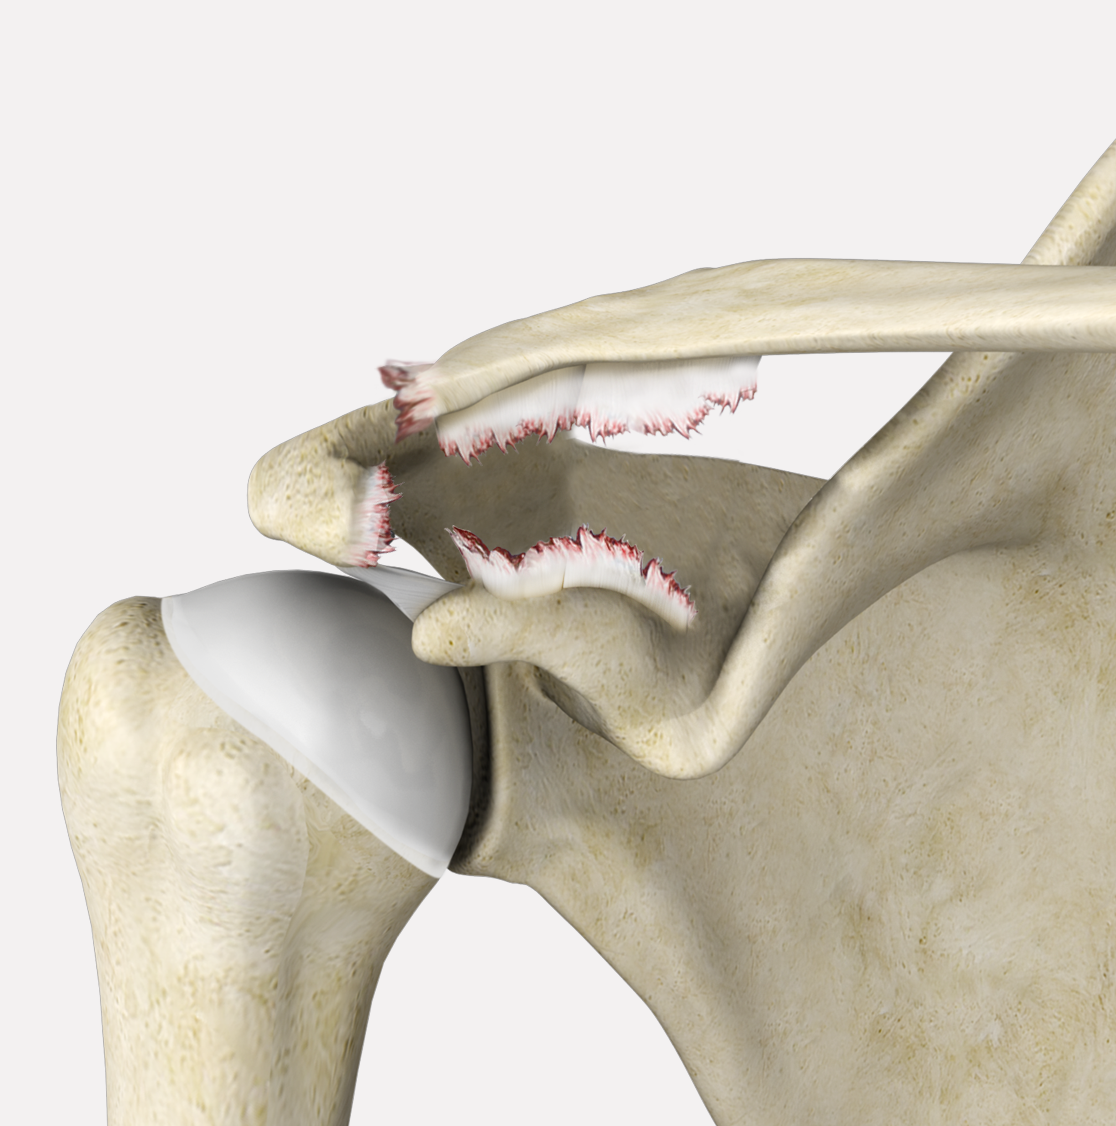

Rotator Cuff Tear

A rotator cuff tear is an injury where one or more of the tendons in the rotator cuff (the group of muscles and tendons that stabilize the shoulder and enable arm movement) become partially or completely torn.

Rotator Cuff Re-tear

Partial Rotator Cuff Tear

A partial rotator cuff tear is an incomplete tear that involves damage to a part of the tendon.

Irreparable Rotator Cuff Tears

Irreparable rotator cuff tears refer to damage to the rotator cuff tendons that is too severe to be repaired with traditional surgical techniques.